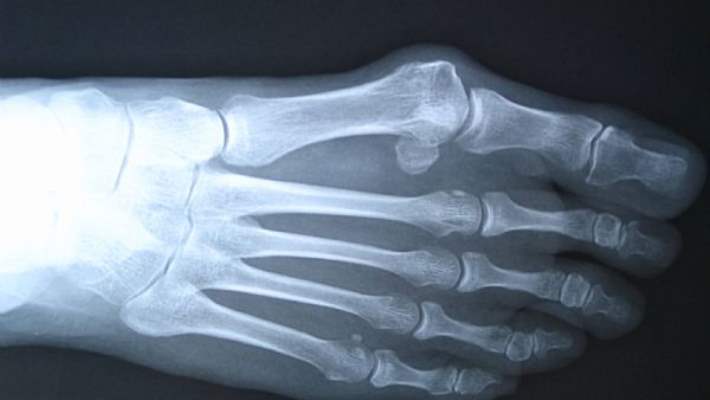

Cam kemik hastalığı, kemiklerde kolay ve sık kırılmanın yanısıra mavi sklera, diş bozuklukları ve işitme bozukluklarının da birlikte görülebildiği bir hastalıktır.

Cam kemik hastalığını başlıca 4 tipi mevcuttur. Tip 2 Cam Kemik hastalıklı çocuklar doğum sonrası erken dönemde kaybedilmektedirler. Yine bu tiplerde Skleraların (göz beyazlarının) beyaz veya mavi olduğu tiplerin yanında, diş bozukluğu olan yada olmayan, işitme bozukluğu ile seyreden cam kemik hastalığı çeşitleri mevcuttur. Cam kemik hastalığı tip 1 kollajen yapısında bozukluk şeklinde çocukluk çağında bulgu vermektedir. Çoğu zaman ilk bulgu tekrarlayan kırıklar, mavi sklera, diş bozuklukları şeklinde görülmektedir. Tip 4 formunda hastalık hafif seyretmekte ve bazı hastalarda tekrarlayan kırıklar görülmemektedir.

Cam kemik hastalığında kırık olunca kırık tedavisi yapılmalı, gecikmiş olgularda gözlenen deformiteler düzeltilmelidir. Bunun yanısıra gen tedavisi ve büyüme hormonu ile tedavi konularında çalışmalar sürmektedir. Son yıllarda kırık sıklığını azaltmak için osteoporozda da kullanılan bifosfonatların belli doz ve aralıklarla cam kemik hastalıklı çocuklara verilmesi ile başarılı sonuçlar bildirilmektedir. Bu çocukların mobilizasyonu konusunda fizik tedavi ve rehabilitasyona mutlak ihtiyaç vardır.